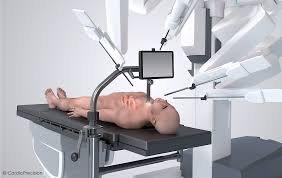

Introduction to Robotic Assisted Surgery Robotic assisted surgery in Korba …

Introduction to Robotic Orthopedic Surgery Robotic orthopedic surgery in Korba …

Introduction to Robotic Hip Replacement Robotic hip replacement in Korba …

Introduction to Robotic Knee Replacement Robotic knee replacement in Korba …

Introduction to Robotic Joint Replacement Robotic joint replacement in Korba …

Introduction to Robotic Assisted Surgery Robotic assisted surgery in Khairagarh-Chhuikhadan-Gandai …

Introduction to Robotic Orthopedic Surgery Robotic orthopedic surgery in Khairagarh-Chhuikhadan-Gandai …

Introduction to Robotic Hip Replacement Robotic hip replacement in Khairagarh-Chhuikhadan-Gandai …

Introduction to Robotic Joint Replacement Robotic joint replacement in Khairagarh-Chhuikhadan-Gandai …

Introduction to Robotic Knee Replacement Robotic knee replacement in Khairagarh-Chhuikhadan-Gandai …